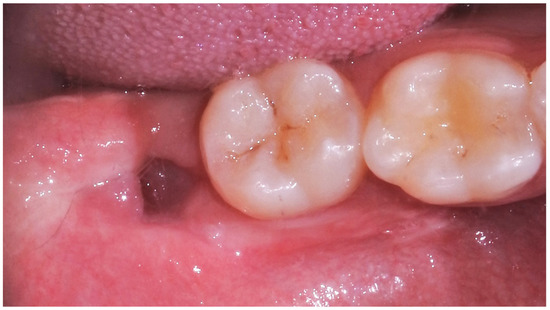

| Inclusion type | Partially impacted Totally impacted | =15 =10 | 60% 40% |